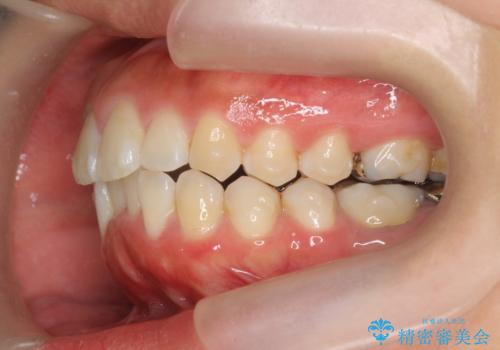

前歯の角度を改善するマウスピース矯正

- 前歯の角度・重なりの改善を求めて矯正治療を希望され来院されました。

通常このような場合、小臼歯を4本抜去しワイヤー矯正を行う治療計画も検討されますが、今回は側方に拡大できる骨量が十分に存在したため抜歯をしない矯正治療の計画を立てます。

しっかりと拡大を行い、IPRも併用したことで歯並びと前歯の角度を大幅に改善することができました。